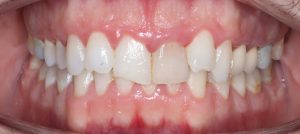

Maloclusión

Se caracteriza por una alineación incorrecta de los dientes, donde los dientes superiores e inferiores están en una relación normal, pero hay una falta de espacio que provoca que los dientes se solapen o estén apiñados.

Este problema puede generar dificultad para mantener una correcta higiene dental y afectar la estética de la sonrisa

FULL

35 Semanas de tratamiento